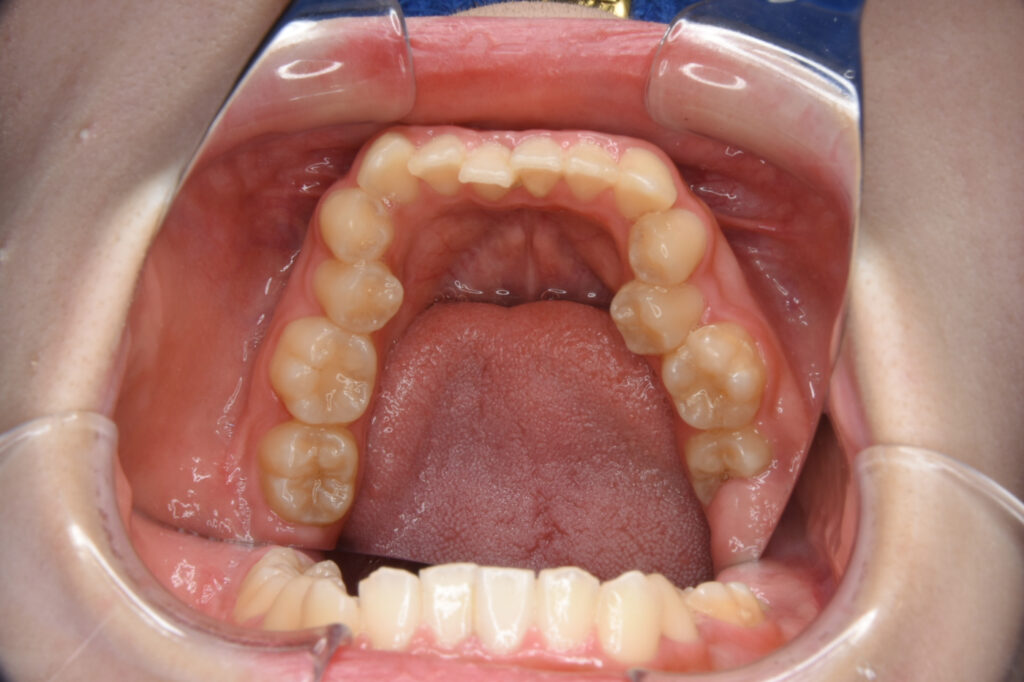

Before

Before

Before

Before